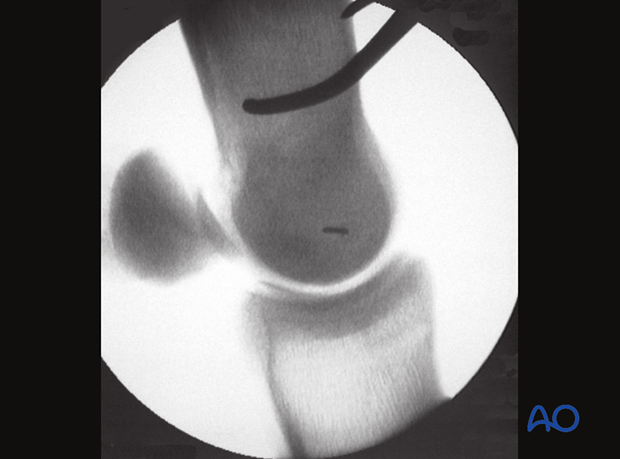

The site of the first screw is the center of the epicondylar fossa. The location of the insertion in the fossa can be estimated by bisecting an imaginary line extending from the palmar/plantar wing of the proximal phalanx to the palpable dorsal edge of the lateral condyle.

A needle should be placed at the selected site and with the help of a lateromedial radiographic/fluoroscopic view its correct location is verified. It is critical to remember that this view is the ONLY view that truly indicates the location for the incision/drill.

Note: The dorsopalmar/plantar view only provides information relative to the height of the needle but not whether is located in the center, at its edge or outside the fossa.